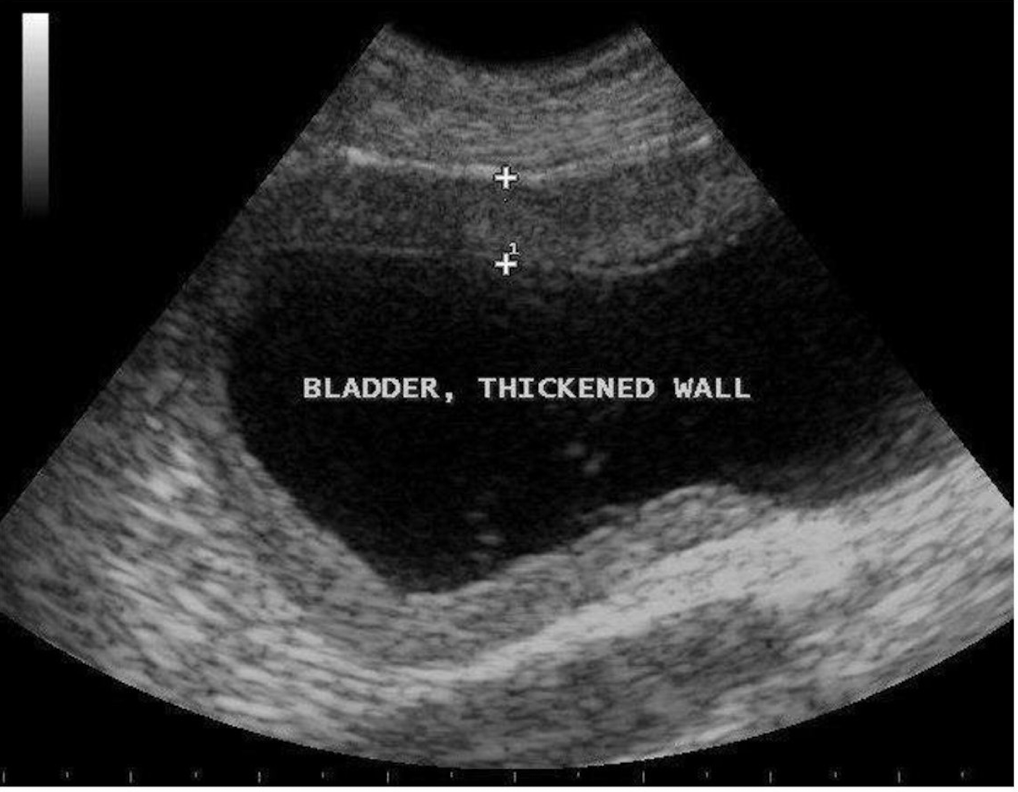

What is being measured here?

the anterior wall of the bladder